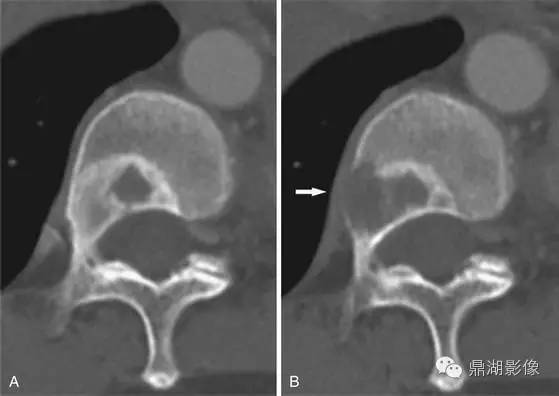

非小细胞肺癌骨转移

X线片表现:好发于肋骨、脊柱、骨盆及颅骨,其次为肱骨、股骨,也有转移至胫、腓、尺、桡及足骨者;破坏灶单发或多发,大多为溶骨性破坏,边缘模糊,骨皮质常有破坏,有时肋骨、坐骨及长骨受累,骨干可完全被破坏吸收而不留痕迹;肺癌成骨性转移很少见,表现为斑点状或絮状密度增高影,密度由毛玻璃状高至象牙质样。部分病例出现软组织肿块,一般无骨膜反应。

2. 骨皮质转移:易侵蚀骨皮质,形成斑片状、碟形或地图样骨缺损,以肱骨、股骨近端多见,也见于胫骨、尺桡骨。